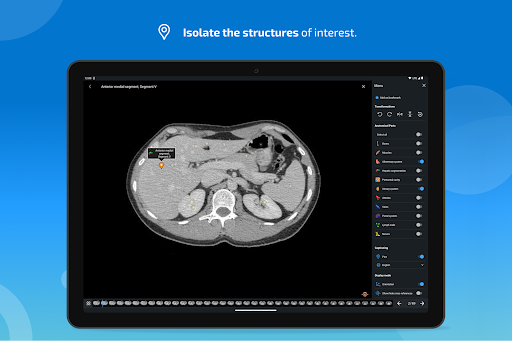

- You can now hide structures one by one (new button inside the description popup) and display them again in the right menu